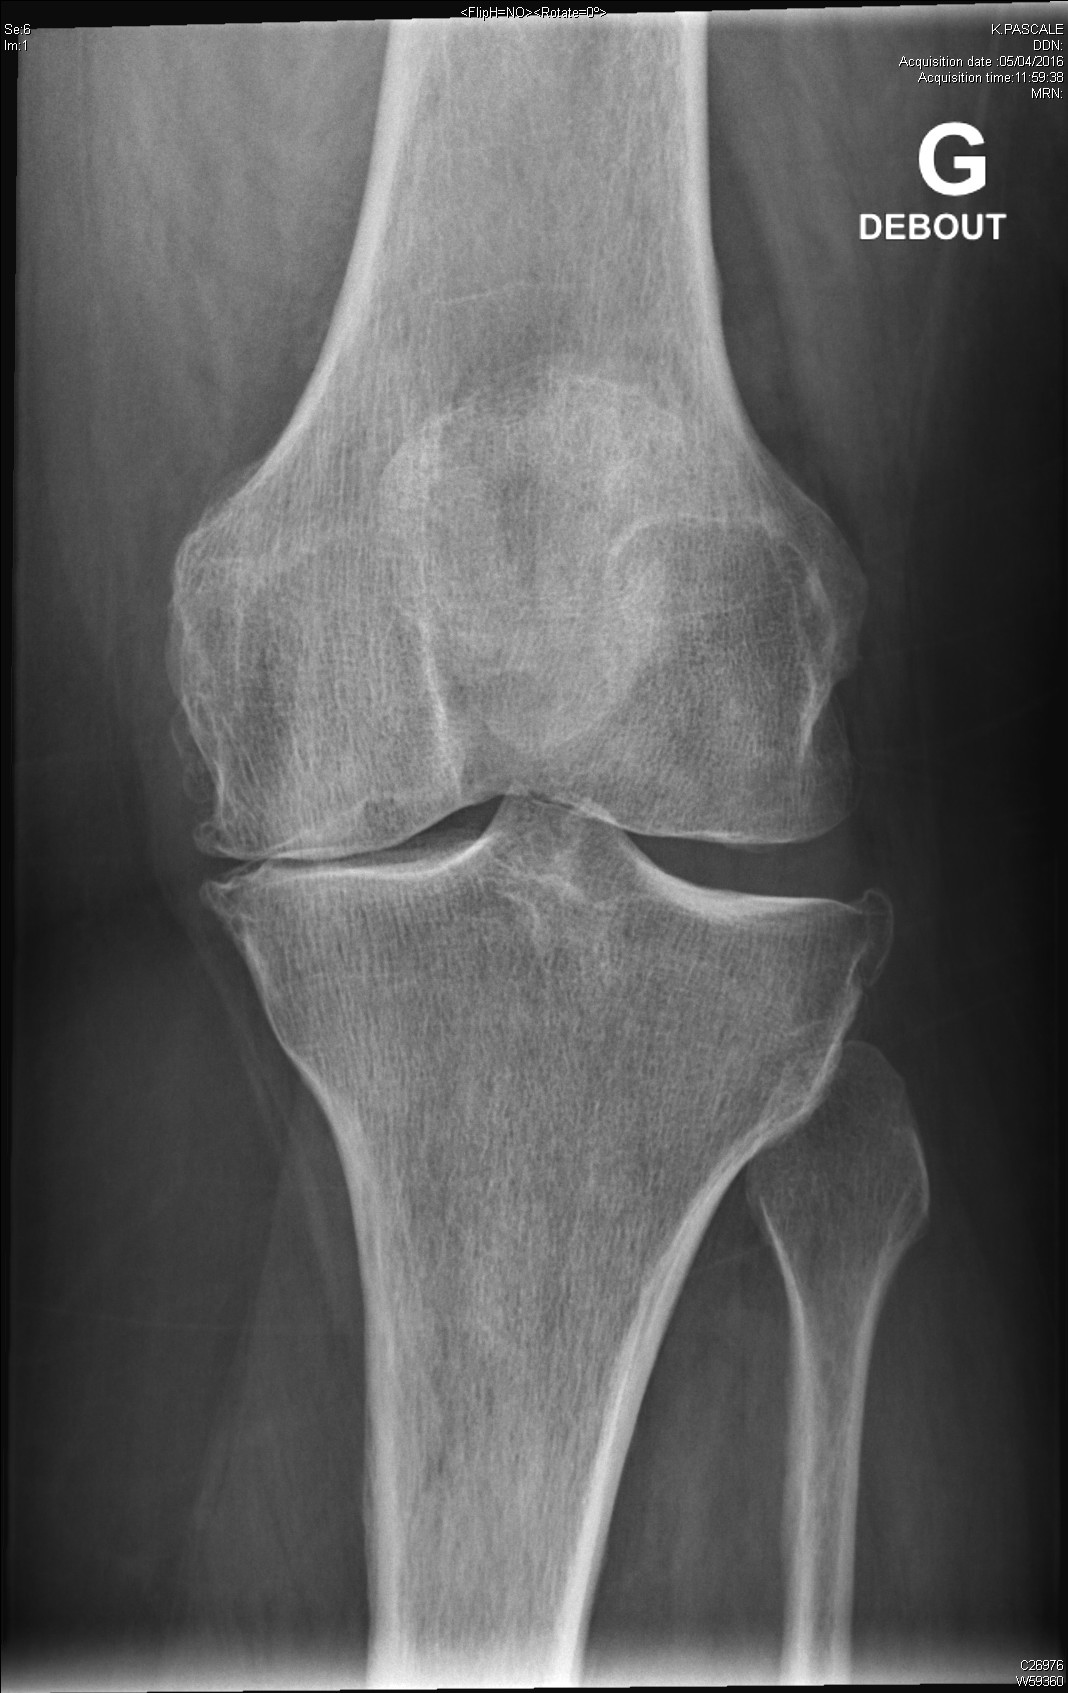

arthrite destructrice évoluée du genou dans le cadre d'une polyarthrite rhumatoïde

Gonarthrose évoluée sur terrain d'obésité